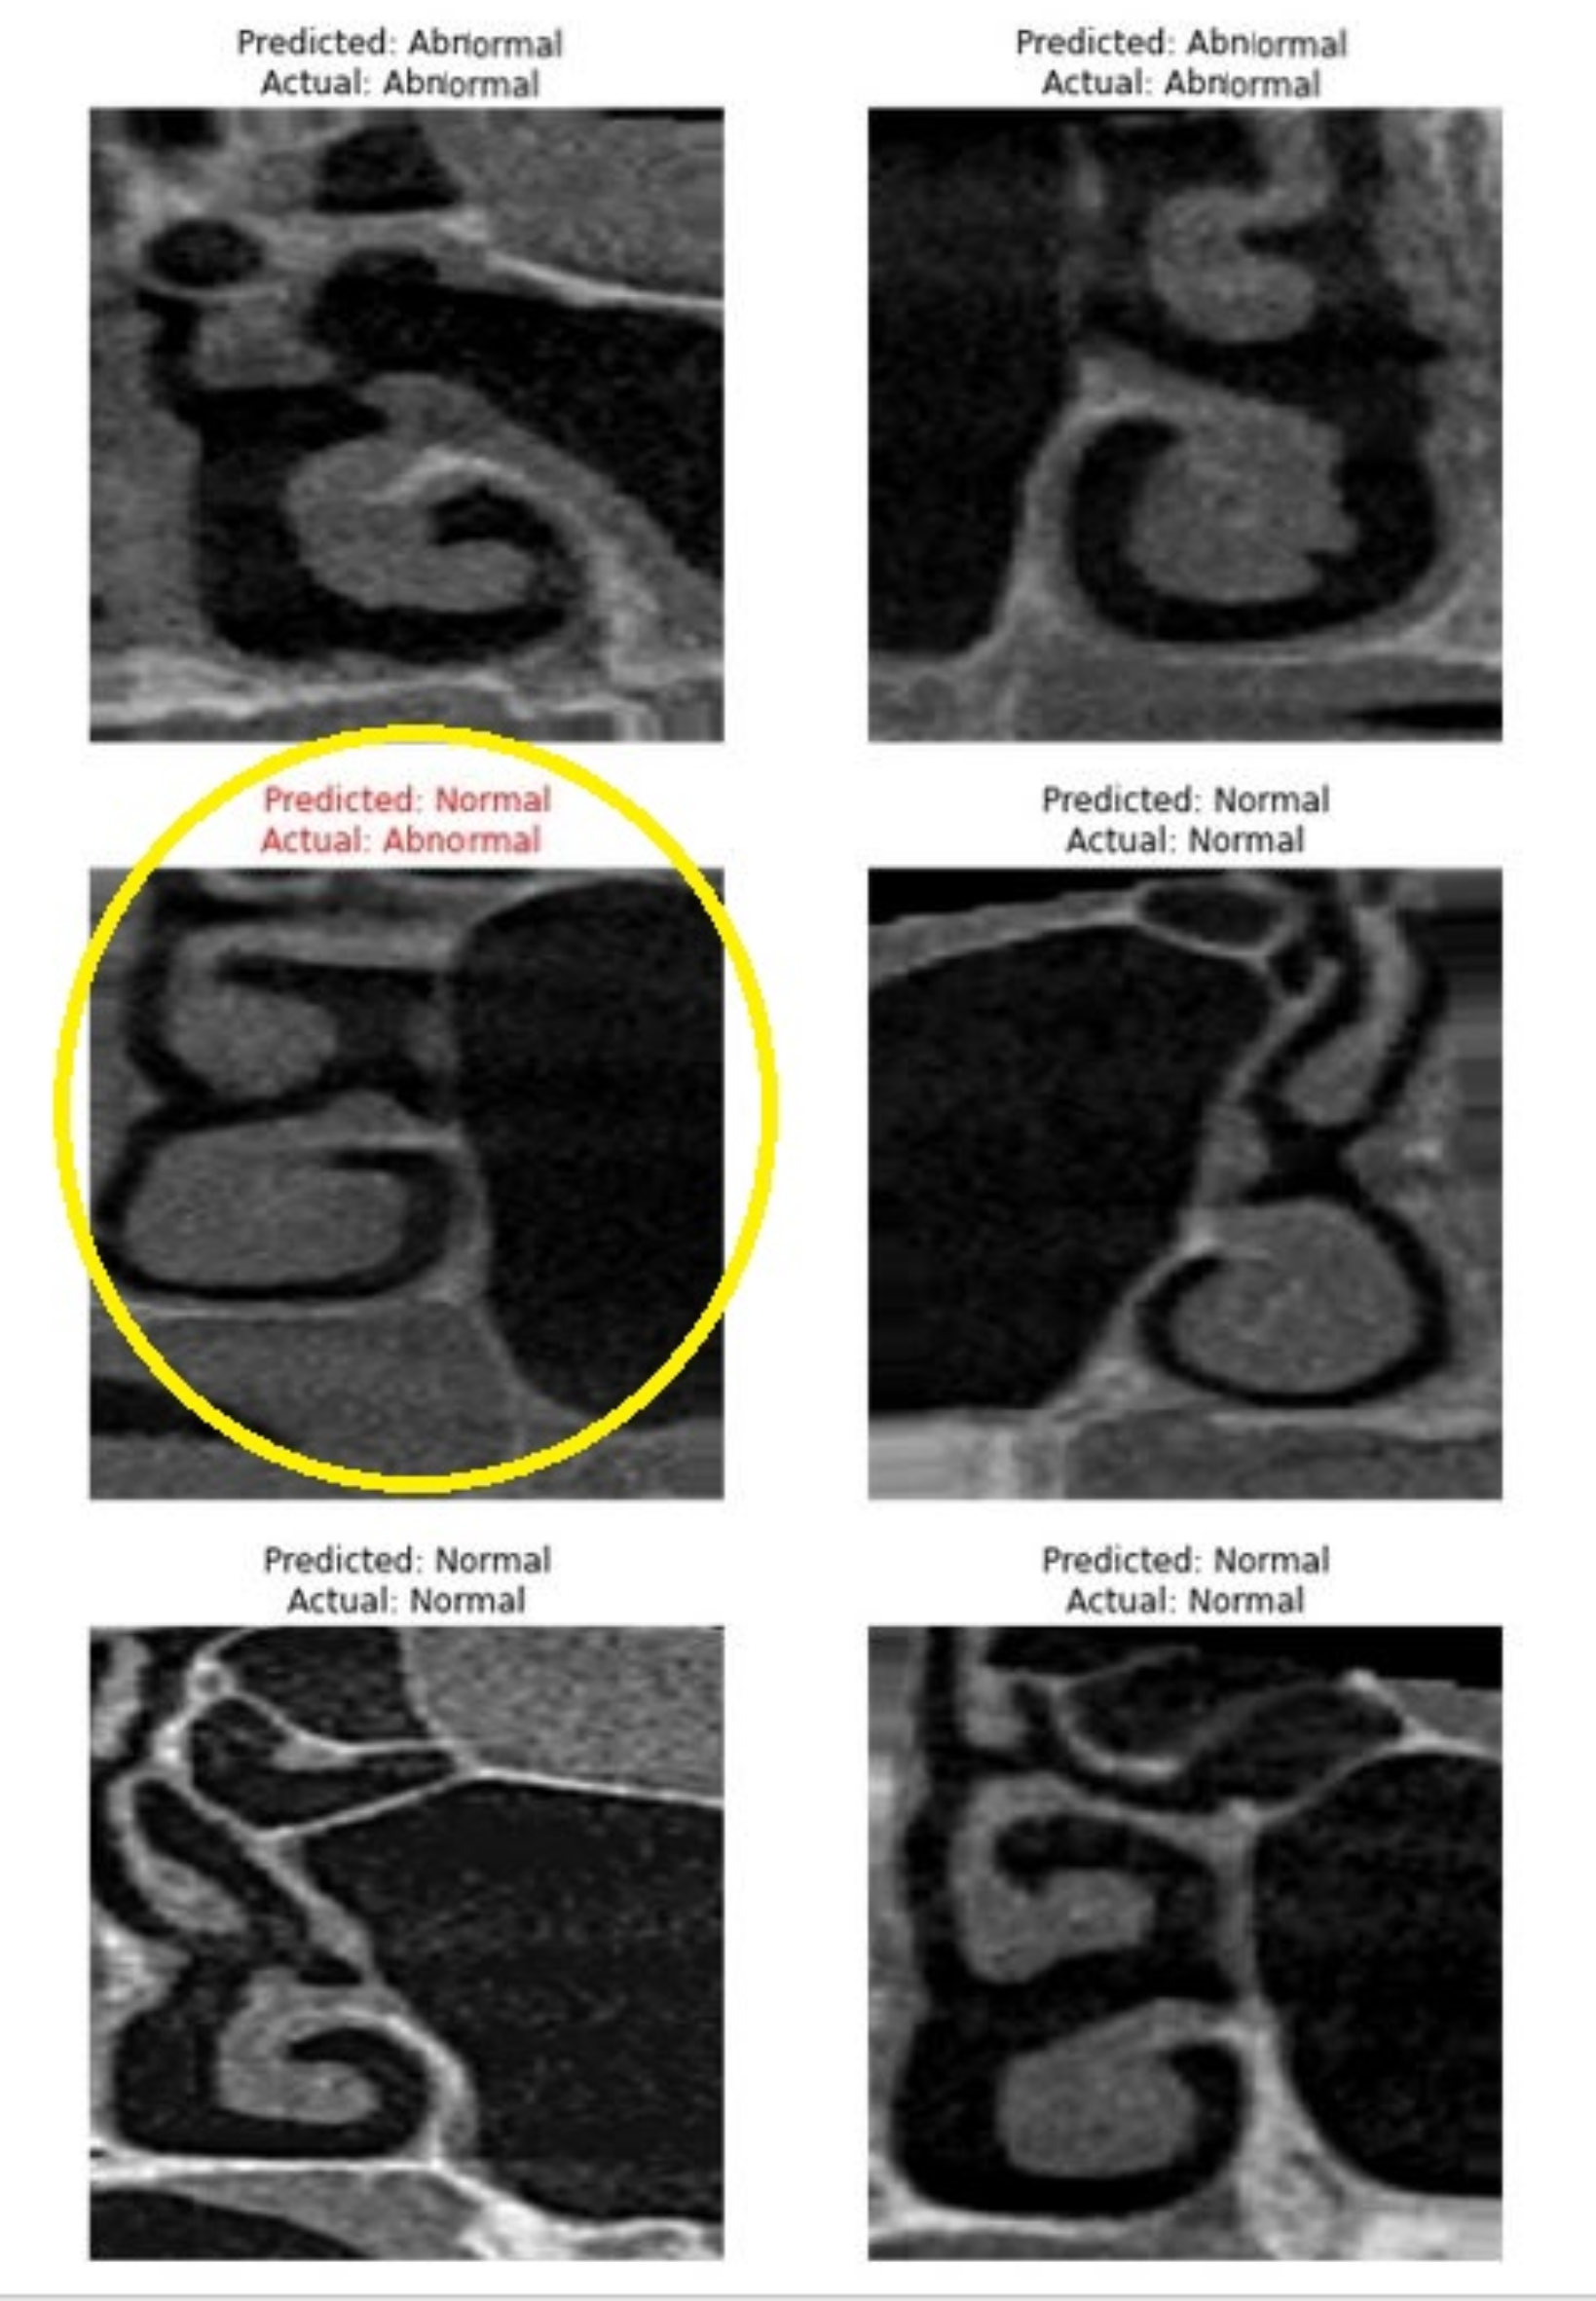

Screenshot of the model classification showing an example of misclassification. Actual abnormal image (with AO) been predicted as normal (without AO) highlighted by yellow circle.